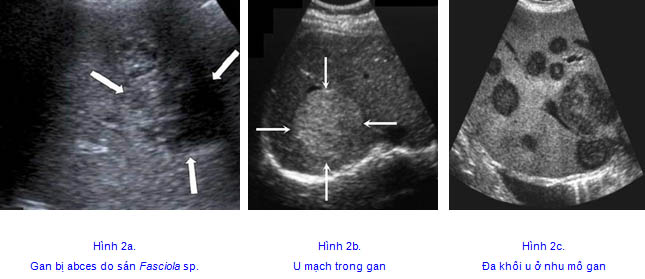

Là các khối tổn thương gan hoặc có kèm theo tổn thương đường mật, có tính chất hồi âm rất khác nhau. Có khối chỉ là một vùng giảm âm, có khối là một vùng tăng âm không đồng dạng dễ nhầm với hình ảnh u mạch, có khối là một vùng lớn với tổn thương thâm nhiễm, tăng âm nhẹ, không có những ổ áp xe, giới hạn tương đối rõ với vùng nhu mô gan lành nên rất dễ nhầm với một khối u gan, nhất là ung thư tế bào gan nguyên phát (HCC_HepatoCellular Carcinoma), hoặc các hình ảnh gan nhiễm mỡ từng phần nhiều mức độ khác nhau.

-Hình ảnh tổn thương gan do SLGL có thể nhầm với một số hình ảnh tổn thương gan ở các bệnh khác:

+Hình ảnh khối tổn thương gan trong ung thư tế bào gan nguyên phát;

+Hình ảnh khối u mạch trong gan, nhất là khi khối u mạch có kích thước lớn hơn 30mm;

+Hình ảnh khối áp xe nhu mô gan ở cả giai đoạn viêm lẫn giai đoạn hoại tử.

Trong một nghiên cứu chi tiết cắt ngang mô tả và tiền cứu về đặc điểm tổn thương gan do SLGL trên siêu âm tại Trung tâm Chẩn đoán Y khoa MEDIC, thành phố Hồ Chí Minh (Phạm Thị Thu Thủy, 2004; Lê Đình Vĩnh Phúc., 2020) đã mô tả hình ảnh tổn thương rõ nét, phần lớn là tổn thương dạng thâm nhiễm với tăng bạch cầu ái toan trong máu ngoại vi. Các tổn thương được mô tả nhiều dạng khác nhau, cấu trúc nhu mô gan không đồng nhất, tổn thương dưới bao gan dạng tụ dịch, nhiều ổ áp xe, tổn thương echo kém, echo dày, có vôi hóa hay không, tổn thương dạng u mạch, hạch rốn gan, dày vách túi mật, vòng Olympic, giả dị vật đường mật đi kèm. Đồng thời, cơ chế gây áp xe bệnh lý do Fasciola sp.cho gan bước đầu đã xác định là gây hoại tử áp xe, gây xơ hóa nhu mô gan, viêm gan khoảng giữa, tổn thương đường mật (nơi định cư của sán). Những thương tổn này có thể nhầm lẫn với một u ác tính hay ung thư tế bào gan nguyên phát (HCC), có thể gặp tổn thương SLGL đồng thời với một khối u lành tính. Hiếm khi thấy được một sán trưởng thành trong túi mật hiện diện dưới dạng một vật thể di động, echo giàu.